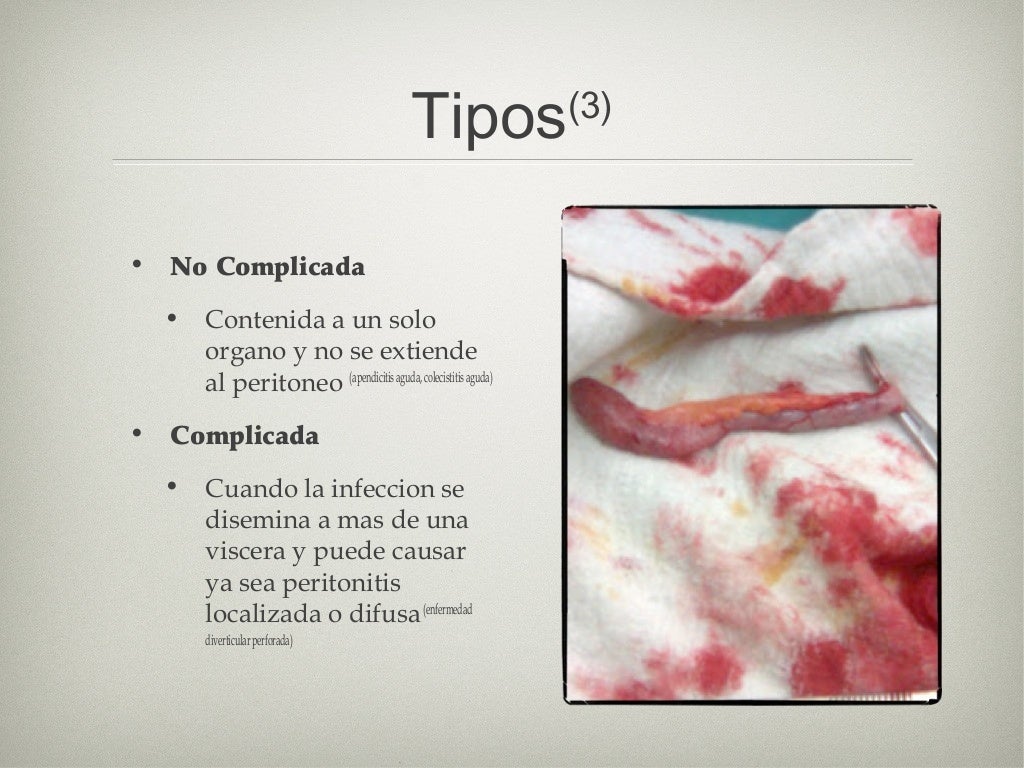

Sepsis intra abdominal

Sepsis intra abdominal

Sepsis intra abdominal